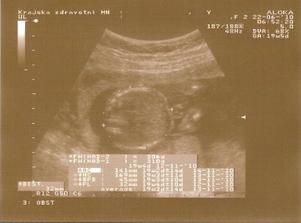

10.5. druhá poradna, prý je dlouho vše v pořádku a tak výsledky z krve říkají, že máme zvýšené riziko na trisomii 21 (Down) - 1:55

11.5. NT screening, jsem 13+5 a teď čekáme.....12.5. výsledky jsou v normě! 🙂